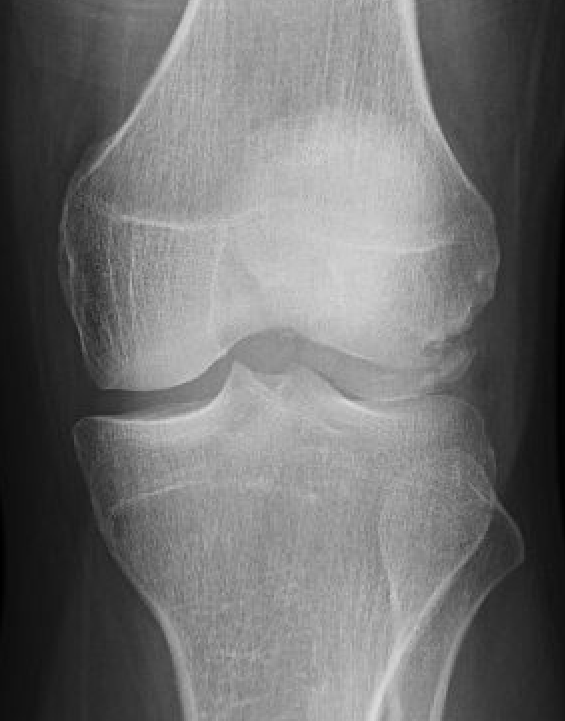

Xray

Look for osteochondral fractures

- AP xray: gutters

Loose body in lateral gutter

Large medial patella osteochondral fracture

Large lateral femoral condyle osteochondral fracture